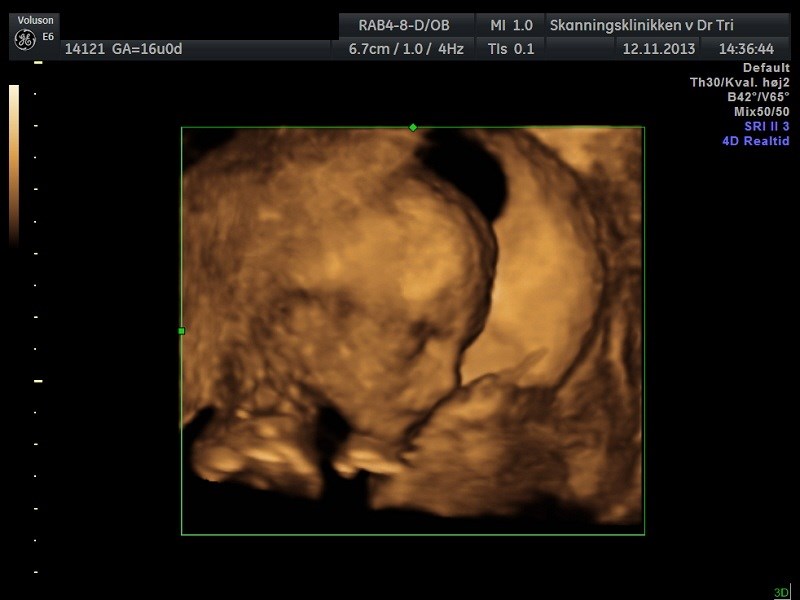

I starten var han meget blufærdig og lå med krydsede ben, men til sidst turde han godt at vise os sine private dele.

Jeg troede at det var en lille pige, som lå derinde, men jeg var åbenbart helt galt på den Så bliver det mors lille dreng i stedet for

Vi fik nogle fine billeder med hjem, og det var skønt at se, at han har det godt. Vi fik også hørt hjertelyd for første gang. Hvor var det bare skønt at få et lille kig til ham.

Vedhæftede fotos (klik for at se i fuld størrelse)